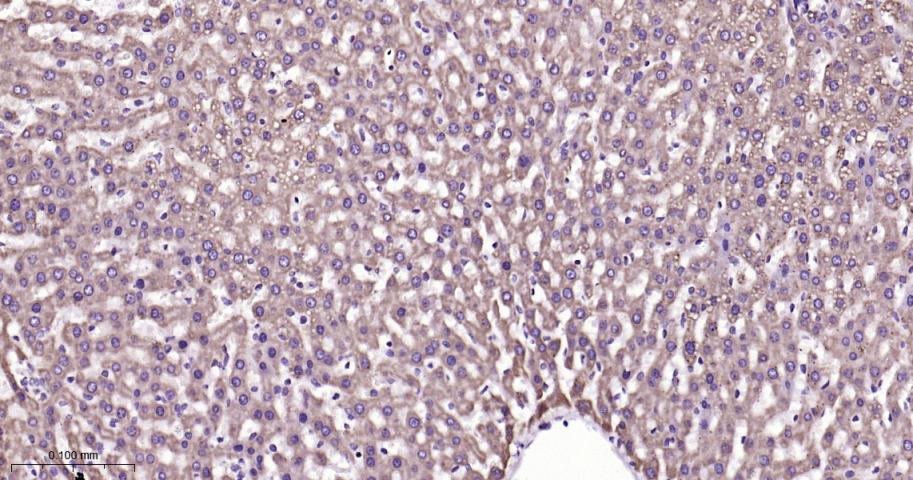

| 英文名称 | VDAC1 Recombinant Rabbit mAb, Mitochondrial Loading Control |

| 产品应用 | WB=1:500-5000, IHC-P=1:100-500, IHC-F=1:100-500, IF=1:100-500, ICC/IF=1:50-200 Not yet tested in other applications. |

| 交叉反应 | Human, Mouse, Rat |

| 背景资料 | Voltage dependent anion selective channel protein 1 (VDAC/Porin) belongs to the eukaryotic mitochondrial porin family and forms a channel through the mitochondrial outer membrane and also the plasma membrane. The channel allows diffusion of small hydrophilic molecules; it adopts an open conformation at low or zero membrane potential and a closed conformation at potentials above 30-40 mV. The open state has a weak anion selectivity whereas the closed state is cation selective. VDAC/Porin expression is observed in the heart,liver and skeletal muscle. |